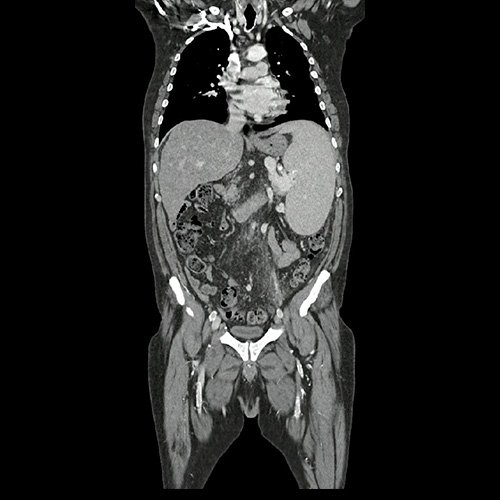

• TAC de abdomen y pelvis con contraste EV (08/25): Se carecen de estudios previos. Se observa hígado de contornos irregulares, con hipertrofia en el lóbulo caudado y el lóbulo hepático izquierdo, con características de hepatopatía crónica, con esteatosis hepática difusa y un patrón de tinción heterogéneo con contraste, no evidenciándose lesiones focales en este examen. Se acompaña este hallazgo de marcada esplenomegalia, homogénea, con un bazo que mide 19 centímetros de diámetro vertical, se observa ingurgitación con prominentes estructuras venosas correspondientes a vena esplénica, circulación colateral venosa periesplénica, y shunts esplenorrenales. La vena porta también se observa aumentada de calibre, con un diámetro de 19 milímetros a nivel del hilio hepático. Vesícula esclero-atrófica con múltiples litiasis que moldean la luz vesical. No se observan lesiones en el páncreas, glándulas suprarrenales y riñones, se observa efecto de masa del bazo sobre el riñón izquierdo. Llama la atención marcada alteración con reticulación de la grasa peritoneal, tanto en el peritoneo anterior como principalmente engrosamiento de las fascias lateroconales y del peritoneo posterior, que se extiende por la grasa mesentérica hacia la pelvis, con ingurgitación de estructuras vasculares venosas pelvianas dependientes de la mesentérica inferior hacia la vena esplénica. No se observa ascitis al momento del examen. El tubo digestivo muestra el estómago colapsado de paredes no evaluables. El colon muestra abundante materia fecal, se observa un área de engrosamiento parietal del colon sigmoides que en primera instancia interpreto como falta de distensión. No se observan adenomegalias, existen ganglios aumentados en número a nivel del mesenterio y del retroperitoneo. No se observan adenomegalias ilíacas o inguinales. Severa ateromatosis de la aorta abdominal y sus ramas. Se observa menor flujo en la vena femoral y vena ilíaca externa izquierda respecto de la contralateral, si bien no es un estudio angiográfico, sugiero cotejar con eco doppler. Vejiga de paredes finas. Las estructuras óseas muestran incipientes espondiloartrosis y cambios degenerativos facetarios.

Tomografía de abdomen y pelvis con contraste. Corte coronal. VER CUAL